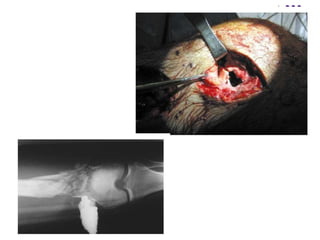

Blast injury